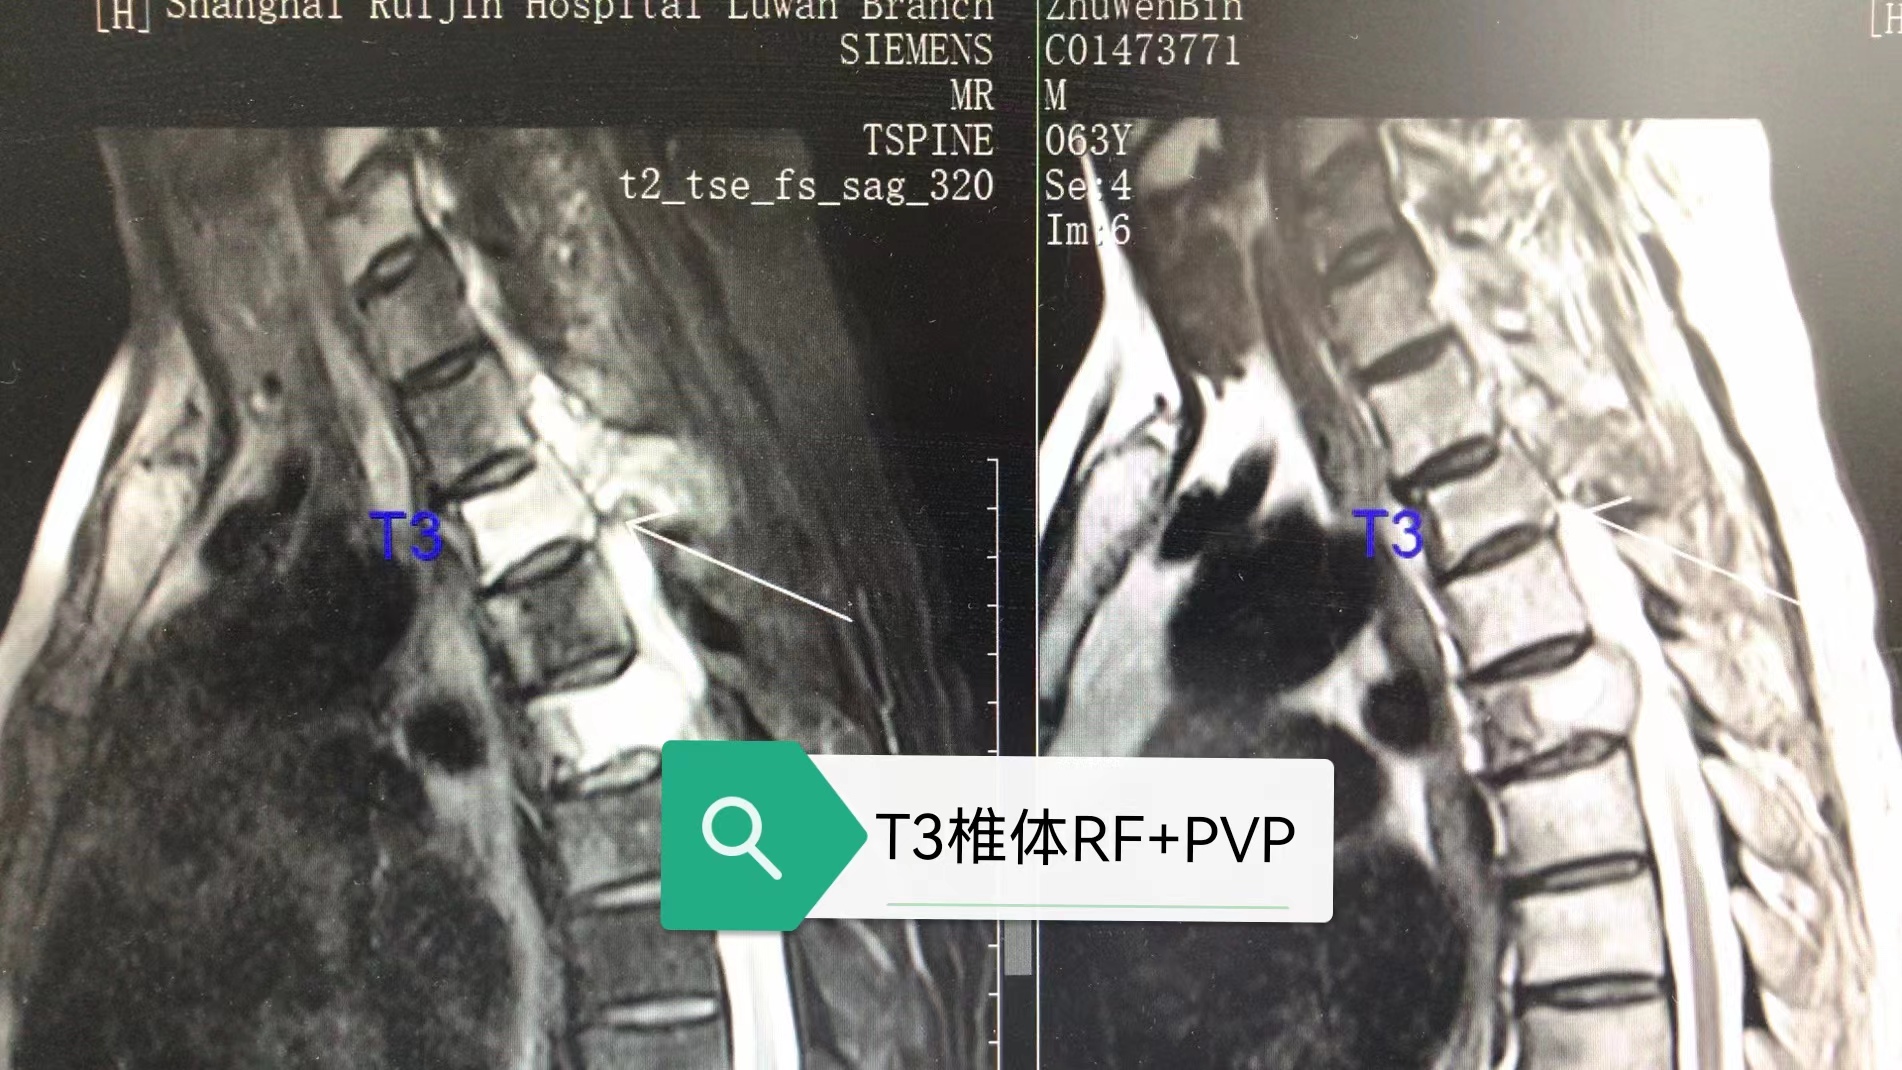

男性病人,63岁,胃Ca、肺Ca并多发椎体转移瘤。MRI及CT提示C6、C7、T3、T5椎体,部分肋骨及右侧肩胛骨骨质信号异常,部分椎体及附件溶骨性破坏伴软组织肿块形成,T2-3、T5水平椎管狭窄伴硬膜外脊髓压迫;C7、T3、T5椎体轻度压缩性改变。

MRI示C6、C7、T3、T5椎体信号异常并软组织肿块